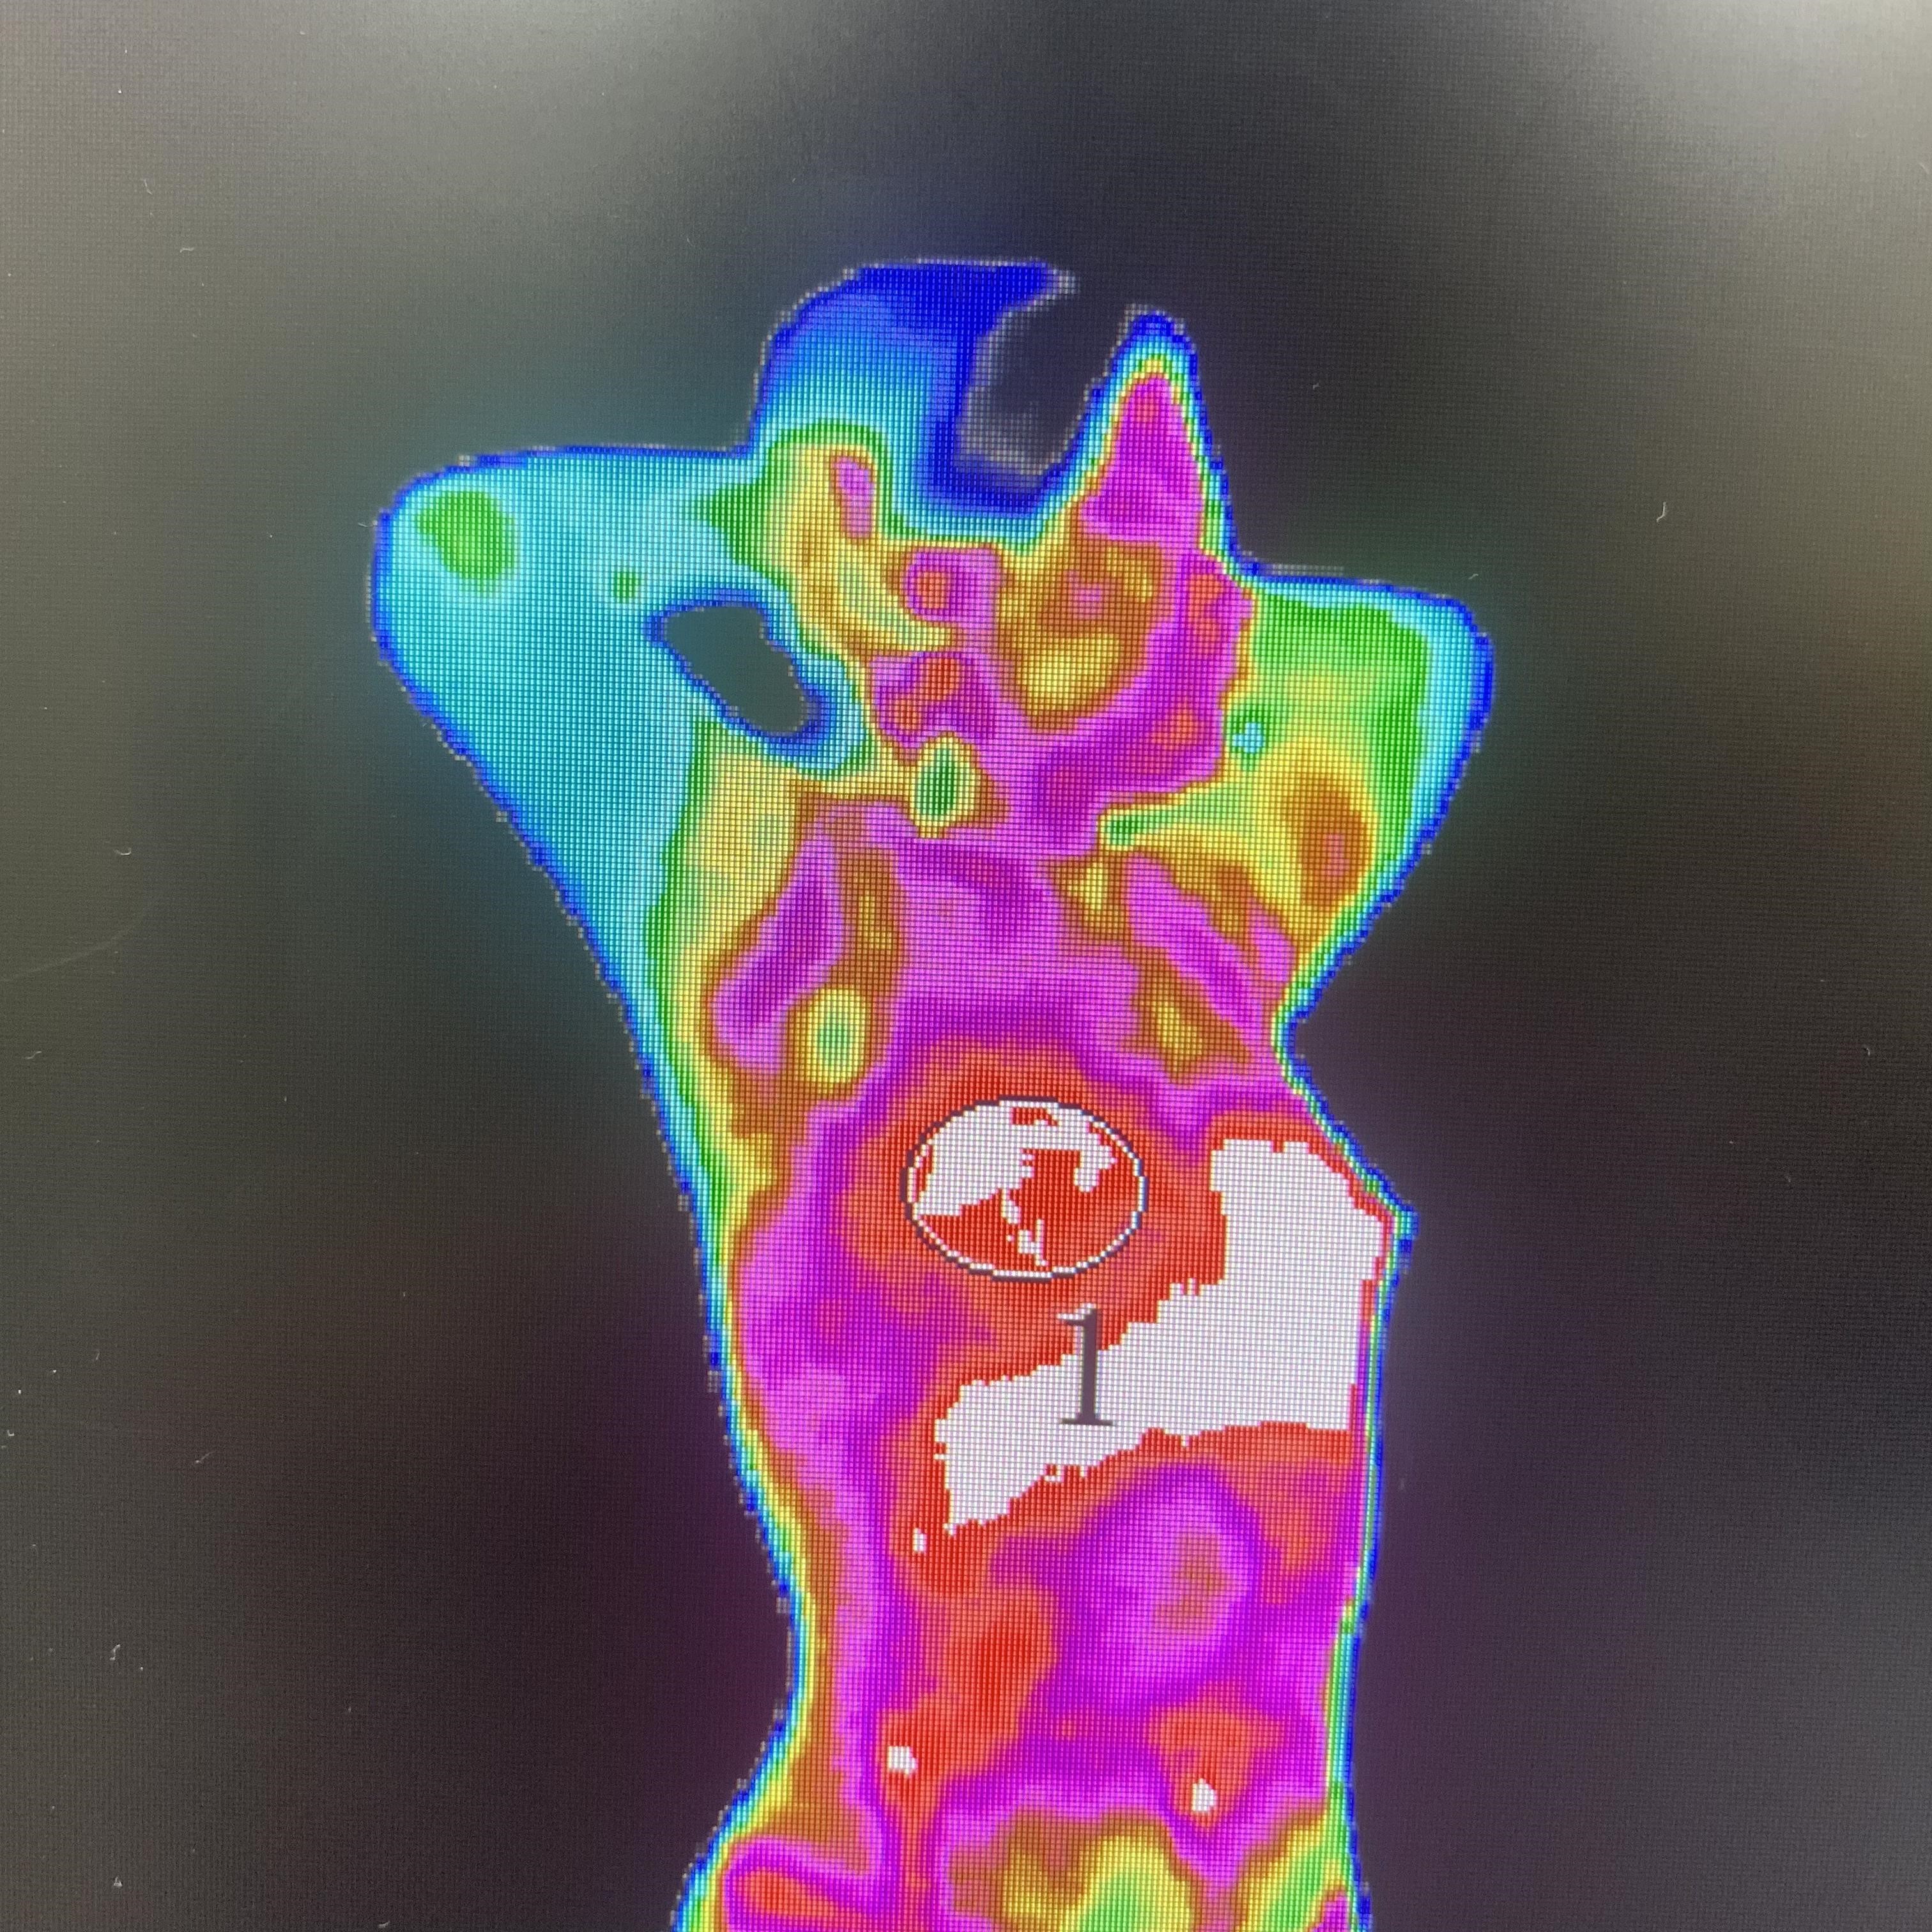

1、全面:TMT红外热成像检查, 可以为受检者从头到脚全身的扫描和评估; 通过红外热成像仪对人体进行全面扫描,将人体体表温度情况用伪色彩图显示出来,专业医生可以结合临床对患者全身情况进行全面系统的分析,克服了其他诊断技术局限于某个局部的片面性。现在应用红外热成像技术已经能够检测炎症、肿瘤、结石、血管性疾病、神经系统疾病等100余种常见病和多发病,涉及人体各个系统;能检查全身各系统的亚健康、亚临床以至于疾病状态的很多不同程度的问题,相当于一次全身“健康精算”。

通过图片画圈地方显示很明显的就会看出哪里出现症状。